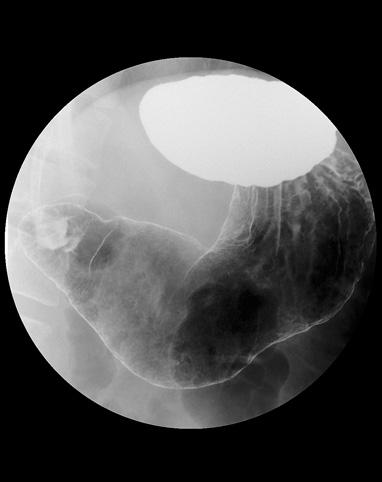

症例提示(所在地,施設名等): 福岡県・ 九州がんセンター

症例登録日 2009/03/31

画像ID:10856

疾患(病理主体)の分類腫瘍様病変/過形成ポリープ

部位(臓器別)胃(部位)/2つ以上

検査方法X-P

病変の最大径(ミリ)10〜14